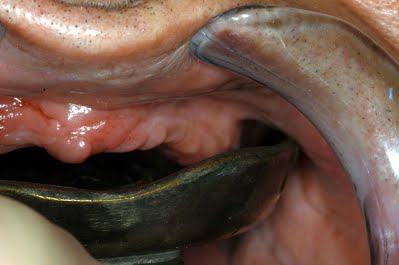

Non - Perforated Impression Trays Set used during fabrication of complete denture

The Waldent Edentulous Non-Perforated Impression Trays K18/2 are crafted from high-quality Rostfrei Stainless Steel. This durable material ensures exc...

They are ideally used with impression compounds to capture accurate impressions of the patient's edentulous arches